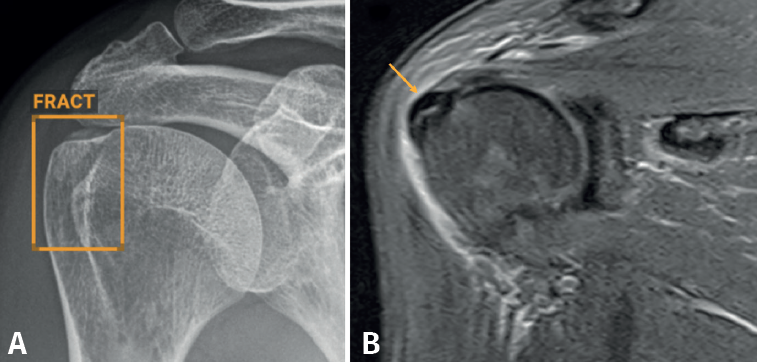

En nuestro caso, decidimos que toda radiografía que llega al PACS se enviara directamente y de manera automática al análisis por la IA, evitando un uso “a demanda” del médico, para favorecer su consulta. El resultado del análisis es devuelto al PACS en un plazo de 1-2 minutos, poniéndolo a disposición del personal médico para su valoración. Los resultados se presentan de manera clara y fácil de interpretar, en 3 niveles: negativo, dudoso o positivo (Figura 2); los dos últimos señalan con un recuadro en la radiografía la imagen de fractura. La diferencia entre un resultado positivo (recuadro con línea continua) y uno dudoso (recuadro con línea discontinua) estriba en un nivel de confianza alto o intermedio para la lesión detectada. Esta solución de IA detecta fracturas en todas las localizaciones anatómicas excepto el cráneo y la columna cervical, y, además, identifica derrames articulares, luxaciones y lesiones óseas. Como control de calidad, se indica el número de imágenes recibidas y el número de imágenes analizadas.

Aunque no hemos realizado un estudio de sensibilidad y especificidad por la complejidad que entraña en la práctica asistencial, consideramos que los resultados son satisfactorios, en línea con lo publicado en la literatura científica. Destacamos la eficacia del algoritmo en la detección de pequeñas fracturas arrancamiento (Figura 3), fracturas de radio distal y proximal (Figura 4), y fracturas múltiples (Figura 5).